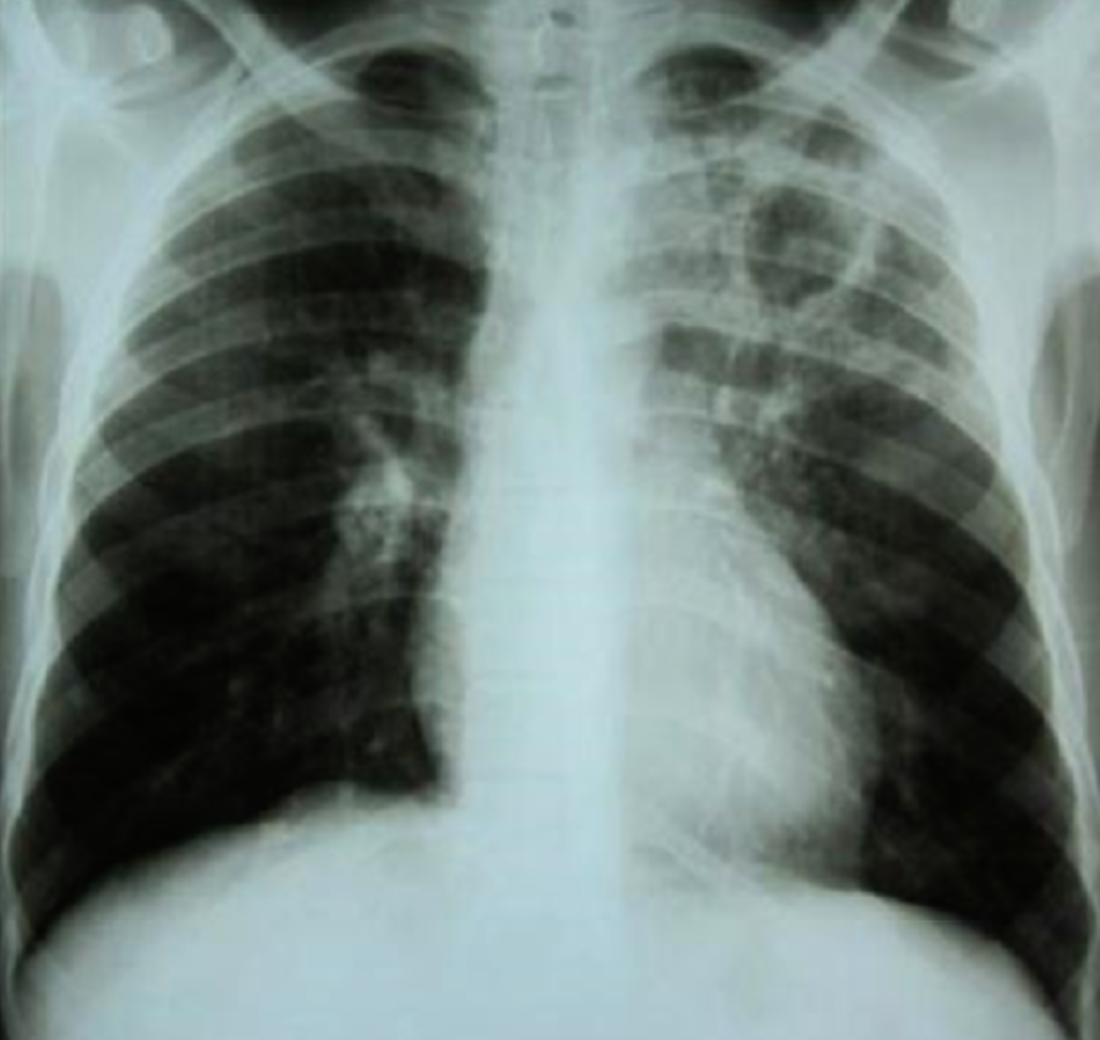

Case 2 Z

A 32 years old male presented with history of low grade fever, cough with sputum, sometimes blood stained. He has weight loss of 5 kg during this period. His chest X-Ray is shown ABOVE.

-

Describe the abnormality seen in the X-Ray?

- Cavitation and consolidation in the left upper lung

- bilateral Hilary lymphadenopathy

What is the likely diagnosis? Pulmonary TB

Mention 2 other investigations which you will advise?

- o Sputum culture and smear

- o IGRA

Mention 2 factors which increase the risk of this disease?

- HIV

- Chemotherapy

Mention 2 drugs used to treat this medical condition?

- o Rifampicin

- o INH (Isoniazid)